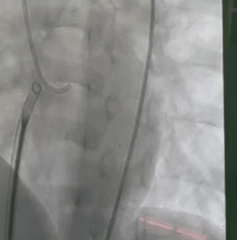

轨道建立

在肺动脉内圈套导丝,建立动静脉轨道

沿导丝送入输送鞘,并将输送鞘压入左心室